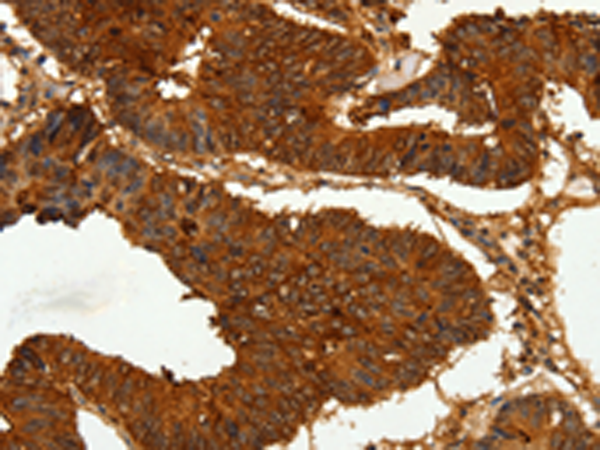

分类: 科研抗体货号: P07187别名: KIP1; MEN4; CDKN4; MEN1B; P27KIP1应用: WB,IHC反应种属: Human, Mouse